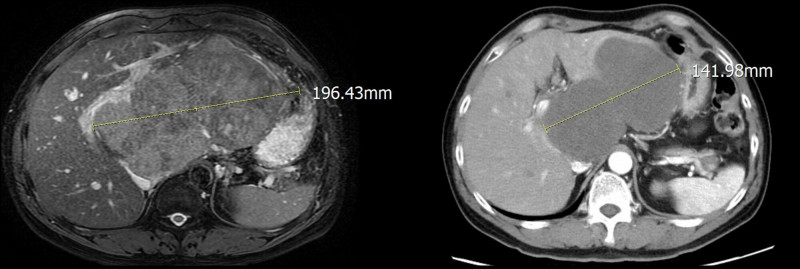

〔記者陳建志/台中報導〕台中51歲吳先生有B型肝炎,但沒有追蹤還持續喝酒,去年底體重爆瘦10公斤就醫檢查,赫然發現左肝長出近20公分大腫瘤,人生頓時變黑白,因壓迫肝門靜脈無法手術,醫療團隊採「四箭療法」,先以標靶藥物、免疫療法、好神刀放射治療將腫瘤縮小剩14公分,再完成切肝手術,患者今天切蛋糕慶重生,強調以後再也不喝酒、抽菸了。

亞大醫院放腫科主任王博民指出,所謂「四箭療法」是透過標靶藥物先控制病情,並搭配免疫治療、好神刀放射治療及切肝手術4種療法,前3種是將腫瘤降階,患者在接受約2個多月治療後,腫瘤縮小剩下約14公分,再由一般外科團隊接手治療。

亞大醫院一般外科主任葉俊杰表示,此次手術最困難的是患者因腫瘤太大,壓迫到肝門靜脈,所幸隨著標靶藥物、免疫療法及精準放療等降階治療,讓腫瘤縮小到安全手術範圍,以傳統手術切除左肝,過程中出血量僅650CC,9天就順利出院。